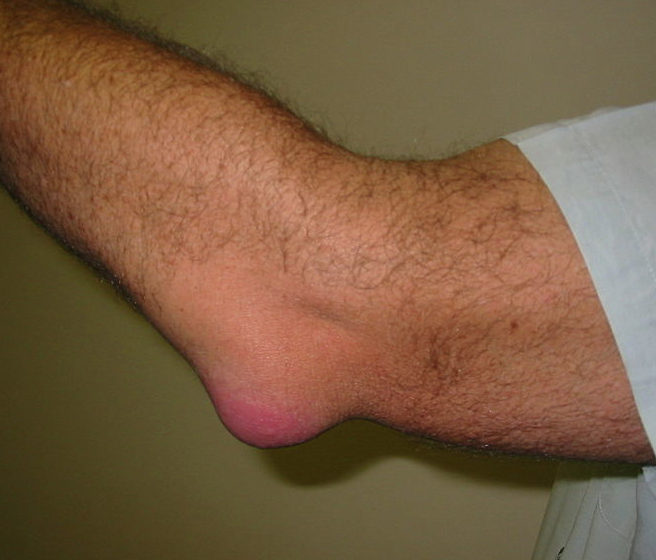

- Olecranon bursitis, "student's elbow", characterised by pain and swelling in the elbow

주두 점액낭염(olecranon bursitis)